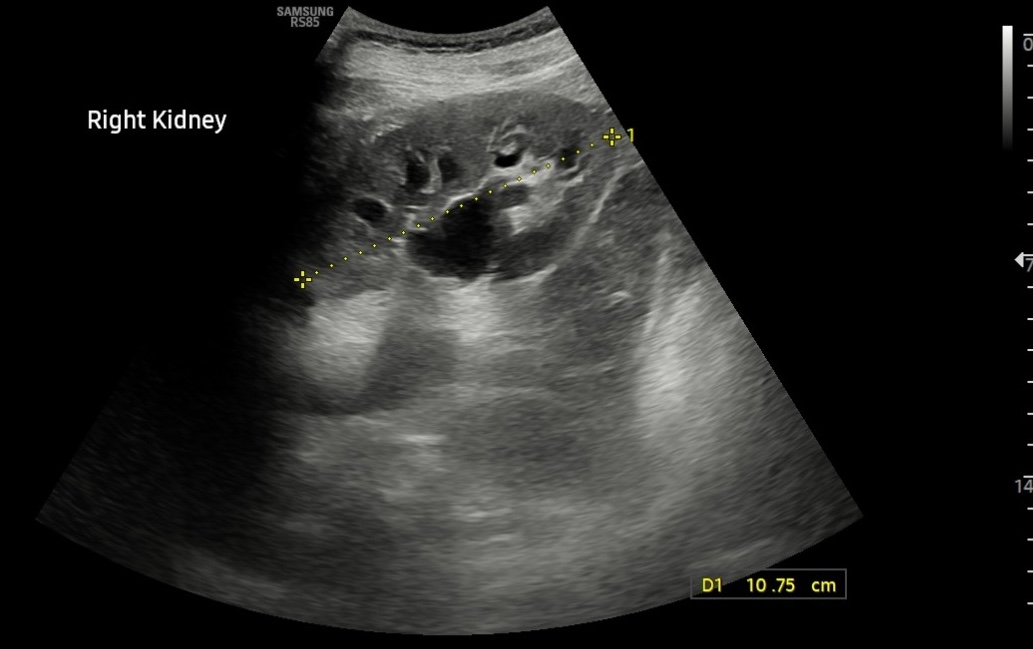

Hallazgos ecográficos

• Ambos riñones de tamaño y parénquima conservados. Objetivamos una hidronefrosis derecha grado 2. Parece apreciarse una imagen compatible con litiasis en uréter proximal y mínima cuña de líquido libre en polo inferior del riñón derecho.